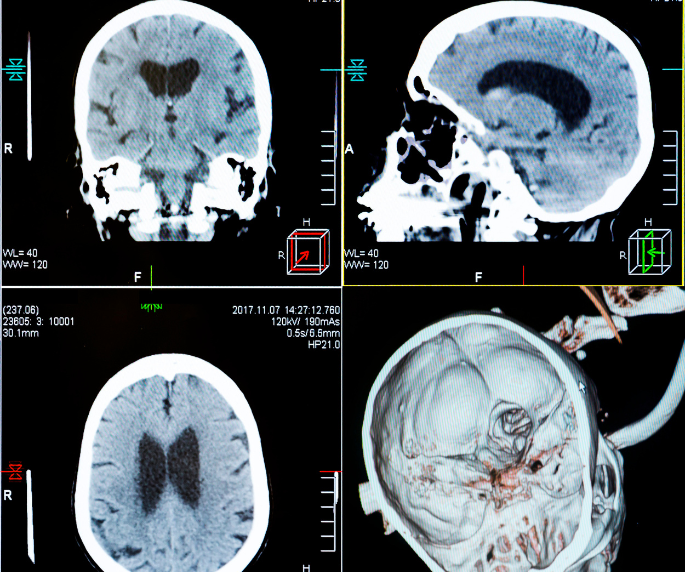

5. Diagnosticando tumores neuroendócrinos.